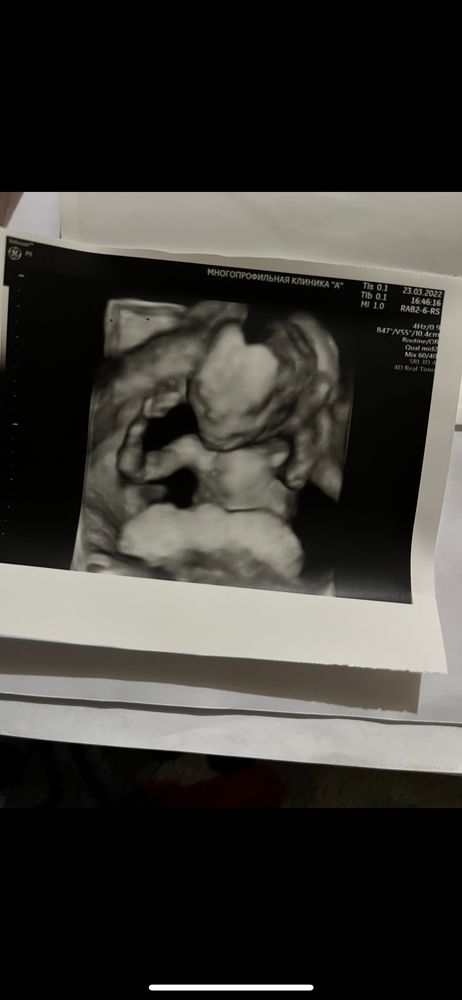

Вот Изображение

Александра, на первом 17 недель